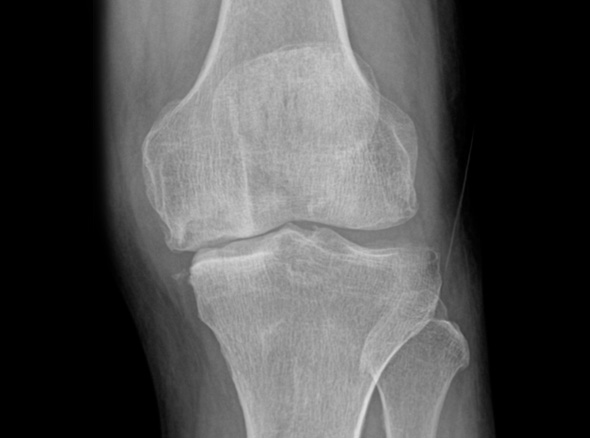

관절 마모 정도가 심하고 통증이 심한 환자분들은 재활치료나 약물만으로는 치료가 어려운 경우가 있습니다.

손상된 무릎 뼈를 제거하고, 그 부위에 특수 소재의 금속 재질로 구성된 인공관절을 삽입하는 수술을 시행할 수 있습니다.

관절연골이 망가져 쓸 수 없을 때 관절기능 회복을 위해 시행하며, 인공관절의 수명은 20~30년 정도 됩니다.

노화로 인해 연골이 닳아 통증,

운동 제한이 발생하는 경우

(계단 오르내리기, 구부리기, 쪼그려 앉기 등)

자가면역질환으로

관절 염증이 심한 경우

골절이나 심한 관절 손상으로

정상적인 기능이 어려운 경우

혈액 공급 장애로 인해

관절 조직이 괴사된 경우